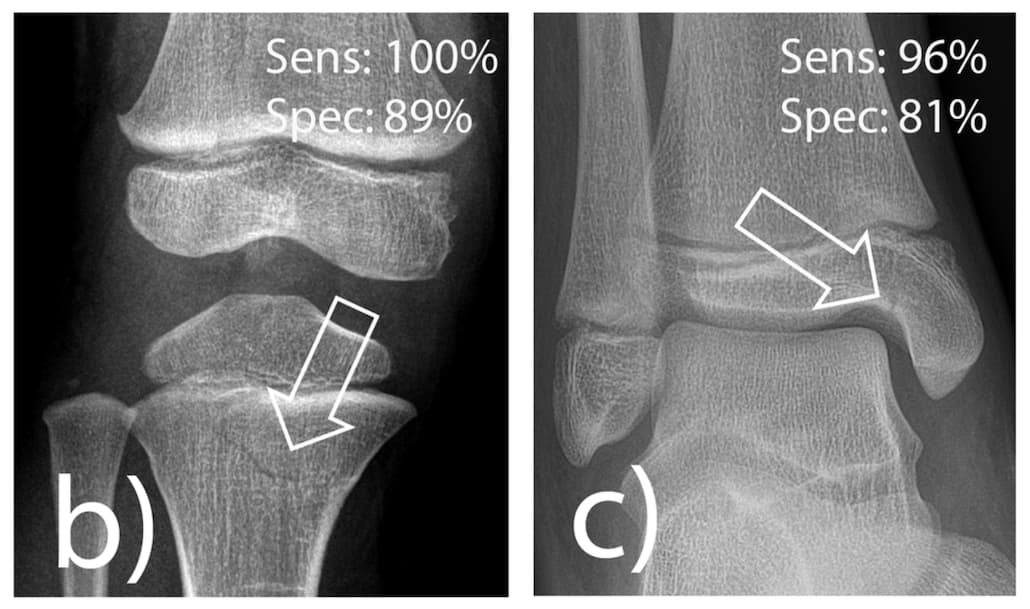

La tomodensitométrie quantitative serait une bonne alternative à l’ostéodensitométrie pour le dépistage de la fracture par déminéralisation osseuse. Pour gagner en précision dans l’évaluation de la DMO par TDM, une étude introduit le deep learning afin de définir une norme d’atténuation trabéculaire...